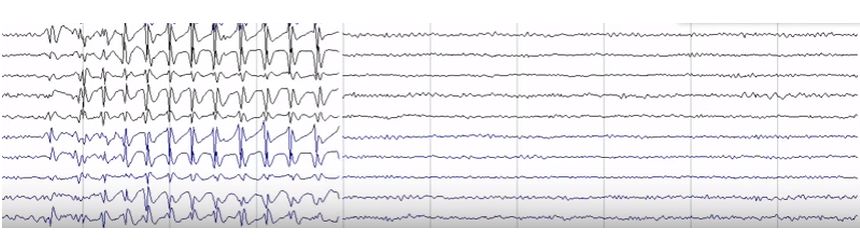

Schizencefalia

Schizencefalia - afecțiune neurologica determinată de o dezvoltare anormală a creierului ce apare între prima și a șaptea lună de gestație. Simptome: microcefalie, macrocranie cu hidrocefalie, paralizii ale membrelor, întârziere în dezvoltarea psihică, convulsii, care în 80% din cazuri apar sub vârsta de 3 ani.